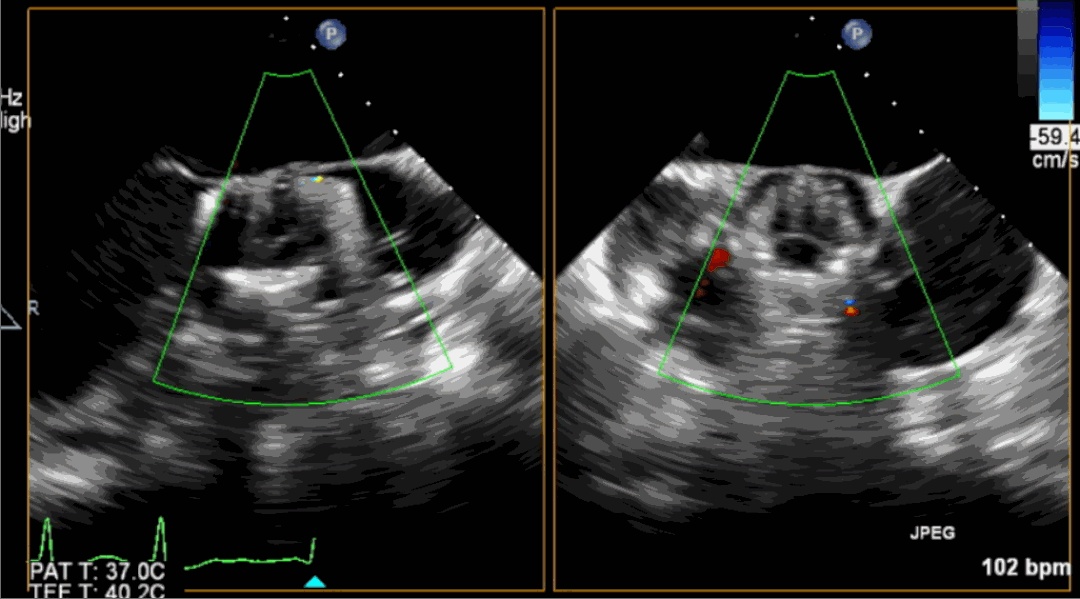

術(shù)前超聲影像圖

術(shù)后超聲影像圖